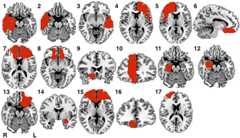

Seventeen patients with a documented temporal relationship between a brain lesion and criminal behavior were identified through a systematic literature search (SI Appendix, Fig. S1 and Table S1). Criminal behaviors included “white collar” crimes, such as fraud or theft; however, most of the patients (12 of 17) had committed violent crimes, such as assault, rape, and murder. Cases included documentation of no criminal behavior before the lesion (15 cases) or resolution of criminal behavior following treatment of the lesion (two cases). The 17 lesions were spatially diverse, including nine in the medial frontal or orbitofrontal structures, three in the medial temporal lobe/amygdala, three in the anterior lateral temporal lobe, one in the dorsomedial prefrontal cortex, and one involving the ventral striatum and parts of the orbitofrontal cortex (Fig. 1). Although the most common lesion location was the vmPFC/orbitofrontal cortex, at least seven lesions were documented to not extend into this area.

Fig. 1.

Lesions temporally associated with criminal behavior. Lesions from 17 patients with acquired criminal behavior, manually traced onto a common brain atlas (MNI).